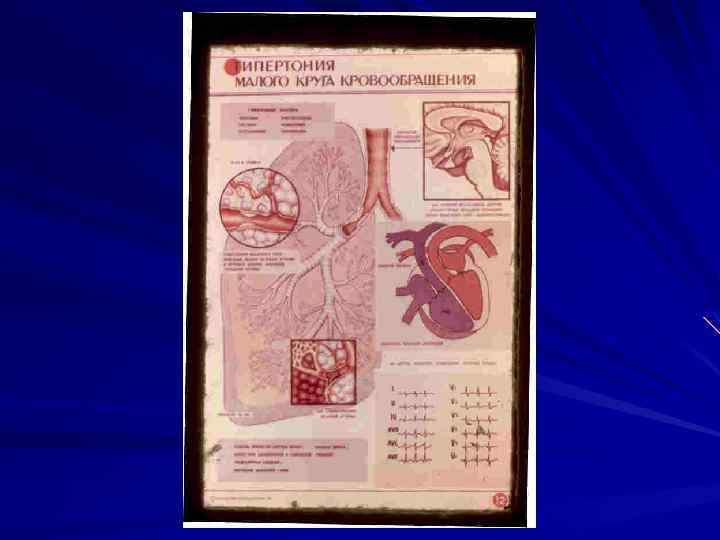

Легочное сердце (сor pulmonale). Определение – патологическое состояние, характеризующееся гипертрофией и (или) дилатацией правого желудочка сердца в результате легочной гипертензии, обусловленной первичными заболеваниями бронхолегочного аппарата, сосудов легких или торакодиафрагмальной патологией.

Классифицируется на: - острое легочное сердце; - подострое легочное сердце; - хроничекое легочное сердце. Стадии: - компенсированное - декомпенсированное (легочно- сердечная недостаточность).